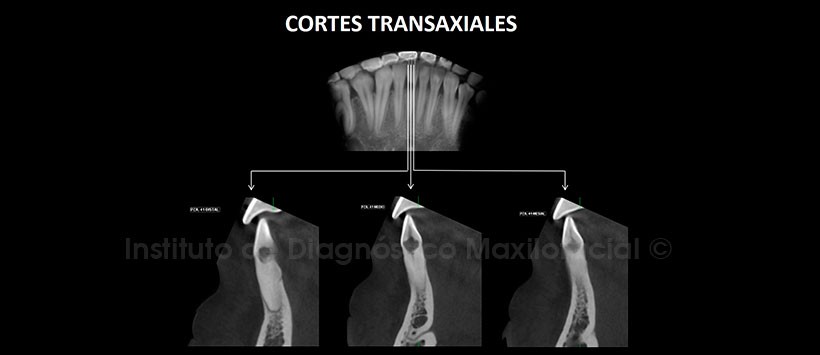

A la evaluación de la radiografía Panorámica (Figura 1) se apreció una imagen radiolúcida de contorno irregular en el tercio cervical de la pieza 41 además de falta de definición del conducto radicular en el tercio medio y apical. A la evaluación de la tomografía computarizada Cone beam mediante cortes axiales, coronales, sagitales (Figuras 2 y 3) y transaxiales (Figura 4), se encontró la presencia de una imagen hipodensa de contorno irregular en el tercio cervical en relación al conducto radicular, que muestra una marcada extensión ocasionando la erosión de la superficie radicular en la zona cérvico distal condicionando comunicación con el espacio periodontal. Signos tomográficos de proceso de reabsorción radicular interna.